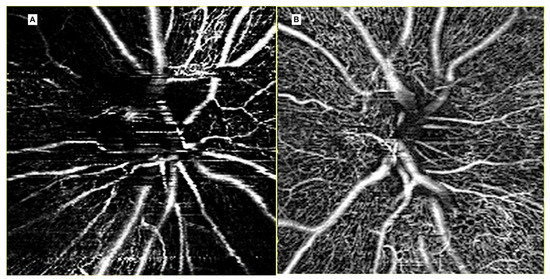

3.1. Radiation (Chorio)Retinopathy

3.2. Radiation Maculopathy